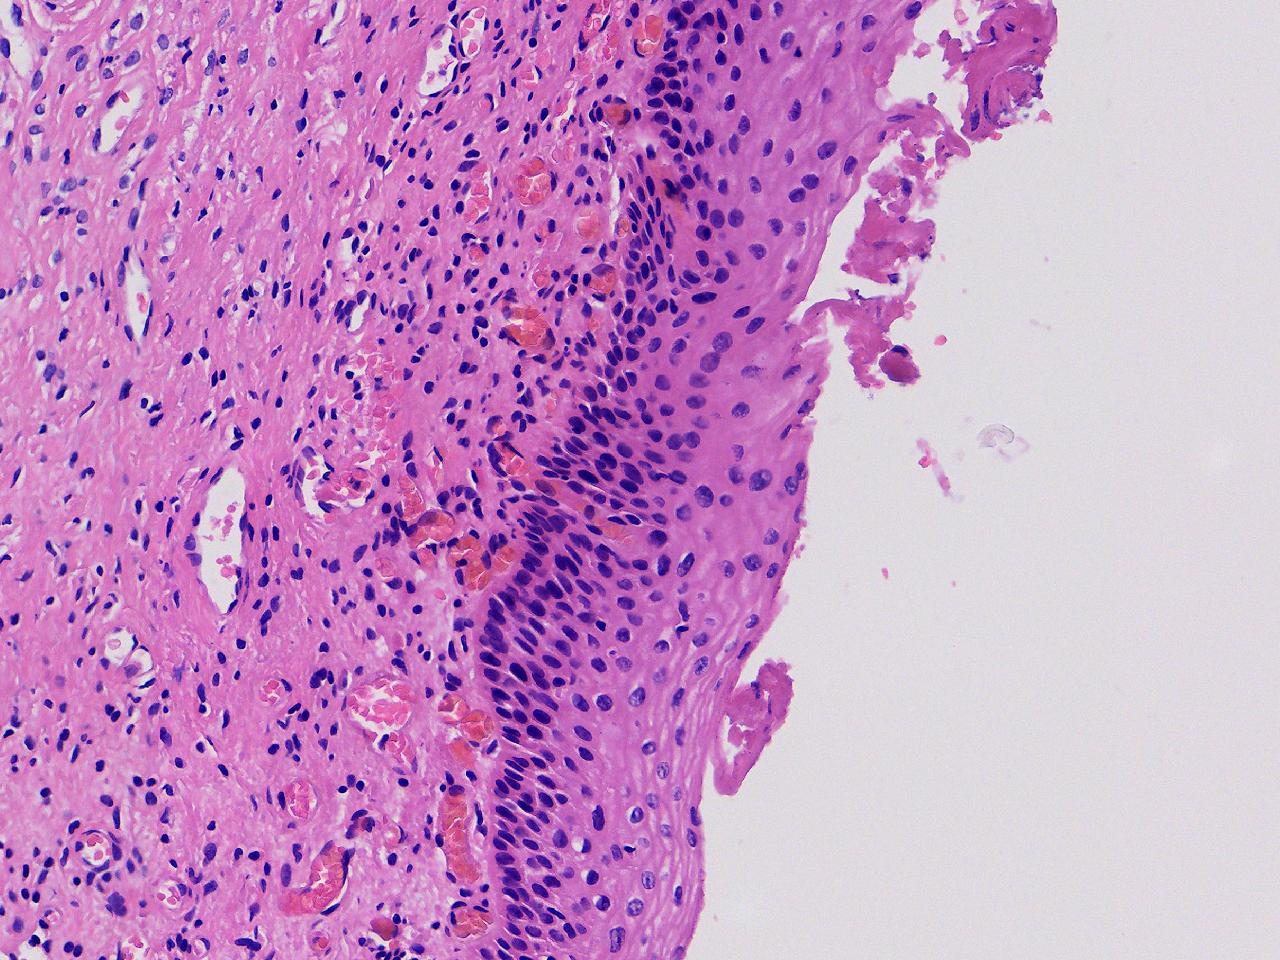

CIN1级? CIN2级?

性别年龄61岁临床诊断

一般病史女,61岁,宫颈活检,,HPV6+ 52+

标本名称宫颈活检

大体所见灰白色不整形软组织1块,直径0.3厘米。

CIN2倒是不够,图3有几个像挖空细胞,HPV有阳,勉强可以考虑小灶LSIL。

• zhuang xia nan:  是的。  2级肯定不够,有挖空细胞,小灶1级。    谢谢老师指点。

CIN1.